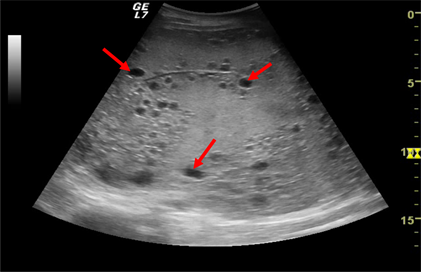

Molar pregnancy is the most common gestational trophoblastic disease. It results from the fecundation of a single egg with no active nucleus, which means all the chromosomes present in the hydatidiform mole are paternal [12] . It was diagnosed in one patient (0.8%) which is less than those found in similar studies [2] [3] [4] [7] . Ultrasound examination showed a heterogeneous echogenic endometrial mass with multiple variable-sized cysts (‘‘Swiss cheese’’ or ‘‘snowstorm’’ endometrium) and no visible embryo (Figure 5).

Figure 5. Complex mass in the uterine cavity with multiple tiny cystic spaces within it (red arrows) compatible with a hydatidiform mole.